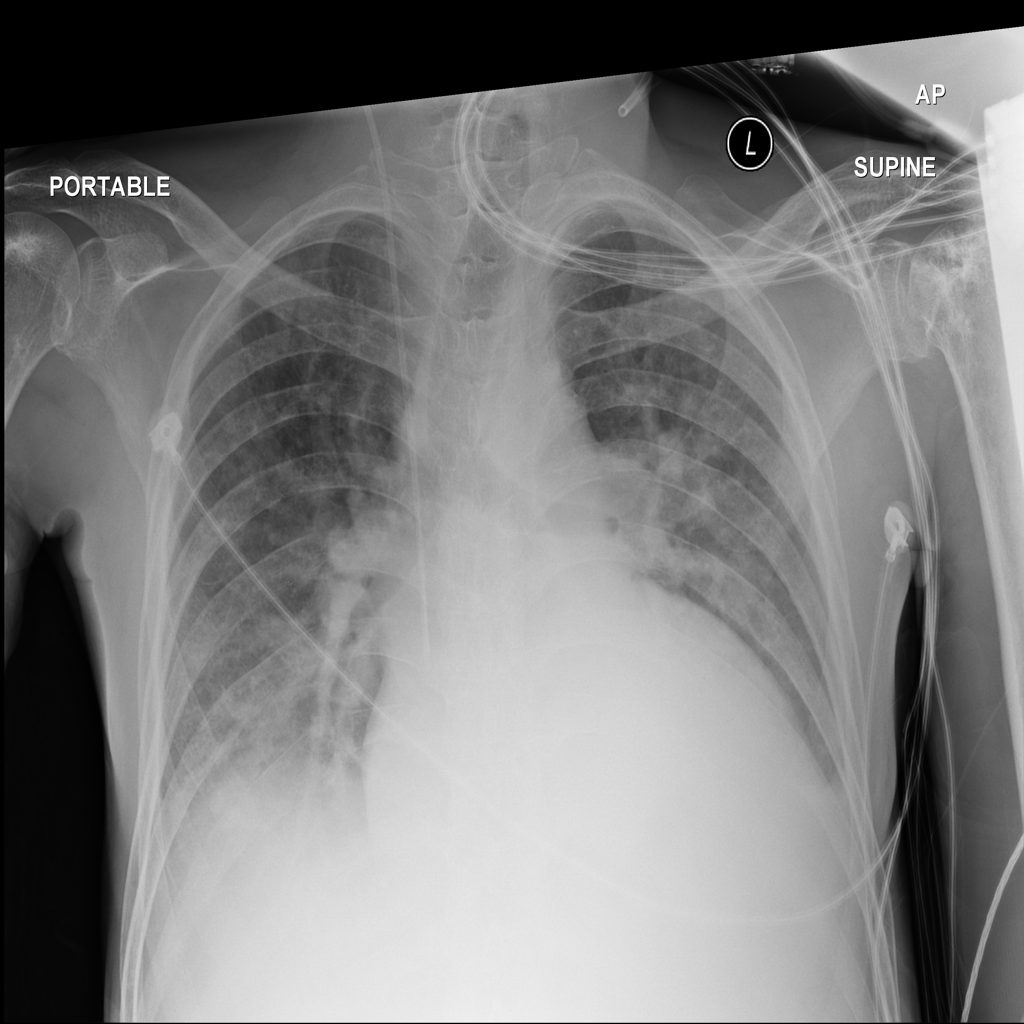

PAT-5B86 · IMG-009Edema

PAT-5B86 · IMG-009

PA